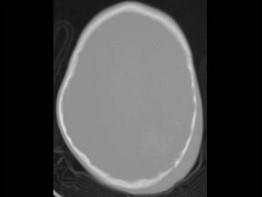

问题 男,3岁,头颅被球击中,请结合CT图像,最选择可能的诊断是 ( )

选项 A、动脉瘤破裂出血 B、血管畸形 C、脑结核 D、脑挫裂伤血肿形成 E、高血压性脑出血

答案 D